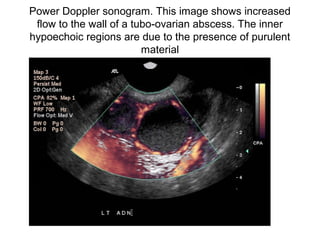

Power Doppler sonogram. This image shows increased

flow to the wall of a tubo-ovarian abscess. The inner

hypoechoic regions are due to the presence of purulent

material